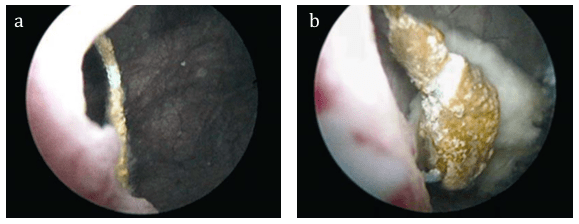

– Litiasis: La presencia de litiasis muchas veces favorece la persistencia de gérmenes en la vía urinaria, pues los antibióticos no son capaces de erradicarlas completamente de las mismas.